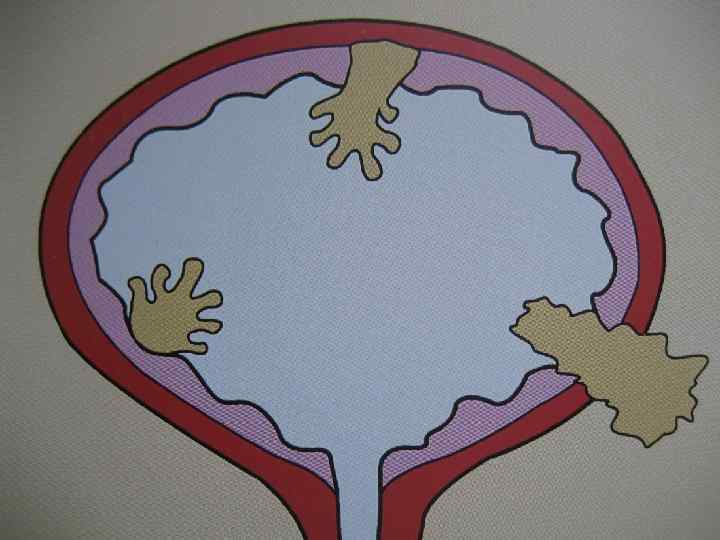

• • Bladder cancer Classification (TNM 97) Ta Non-invasive papillary Tis In situ: 'flat tumour' T 1 Subepithelial connective tissue T 2 Muscularis T 2 a Inner half T 2 b Outer half • T 3 Beyond muscularis T 3 a Microscopically T 3 b Extravesical mass • T 4 Other adjacent structures T 4 a Prostate, uterus, vagina T 4 b Pelvic wall, abdominal wall 16

Опухоль м/п Recomendations • Physical examination (including digital rectal and pelvic examination) • Renal and bladder ultrasonography and/or IVP • Cystoscopy with description of the tumour: size, site, appearance (a diagram of the bladder should be included) • Urinalysis • Urinary cytology • TUR with: • biopsy of the underlying tissue • random biopsies in the presence of positive cytology, large or non-papillary tumour • biopsy of the prostatic urethra in cases of Tis or suspicion of it 24